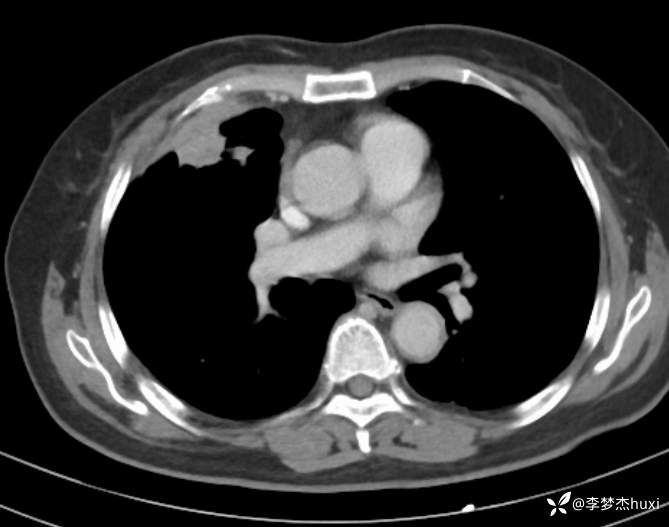

女性69岁,胸痛住院,检查发现肺占位性病变,猜病理

辅助检查:胸部CT:右肺占位?炎症?双肺炎性变,左肺下叶陈旧性病变,双肺纹理增多,主动脉及冠状动脉钙化,双侧胸膜局部增厚,胆囊结石,多发肝囊肿?请结合超声。

临床诊断:肺占位